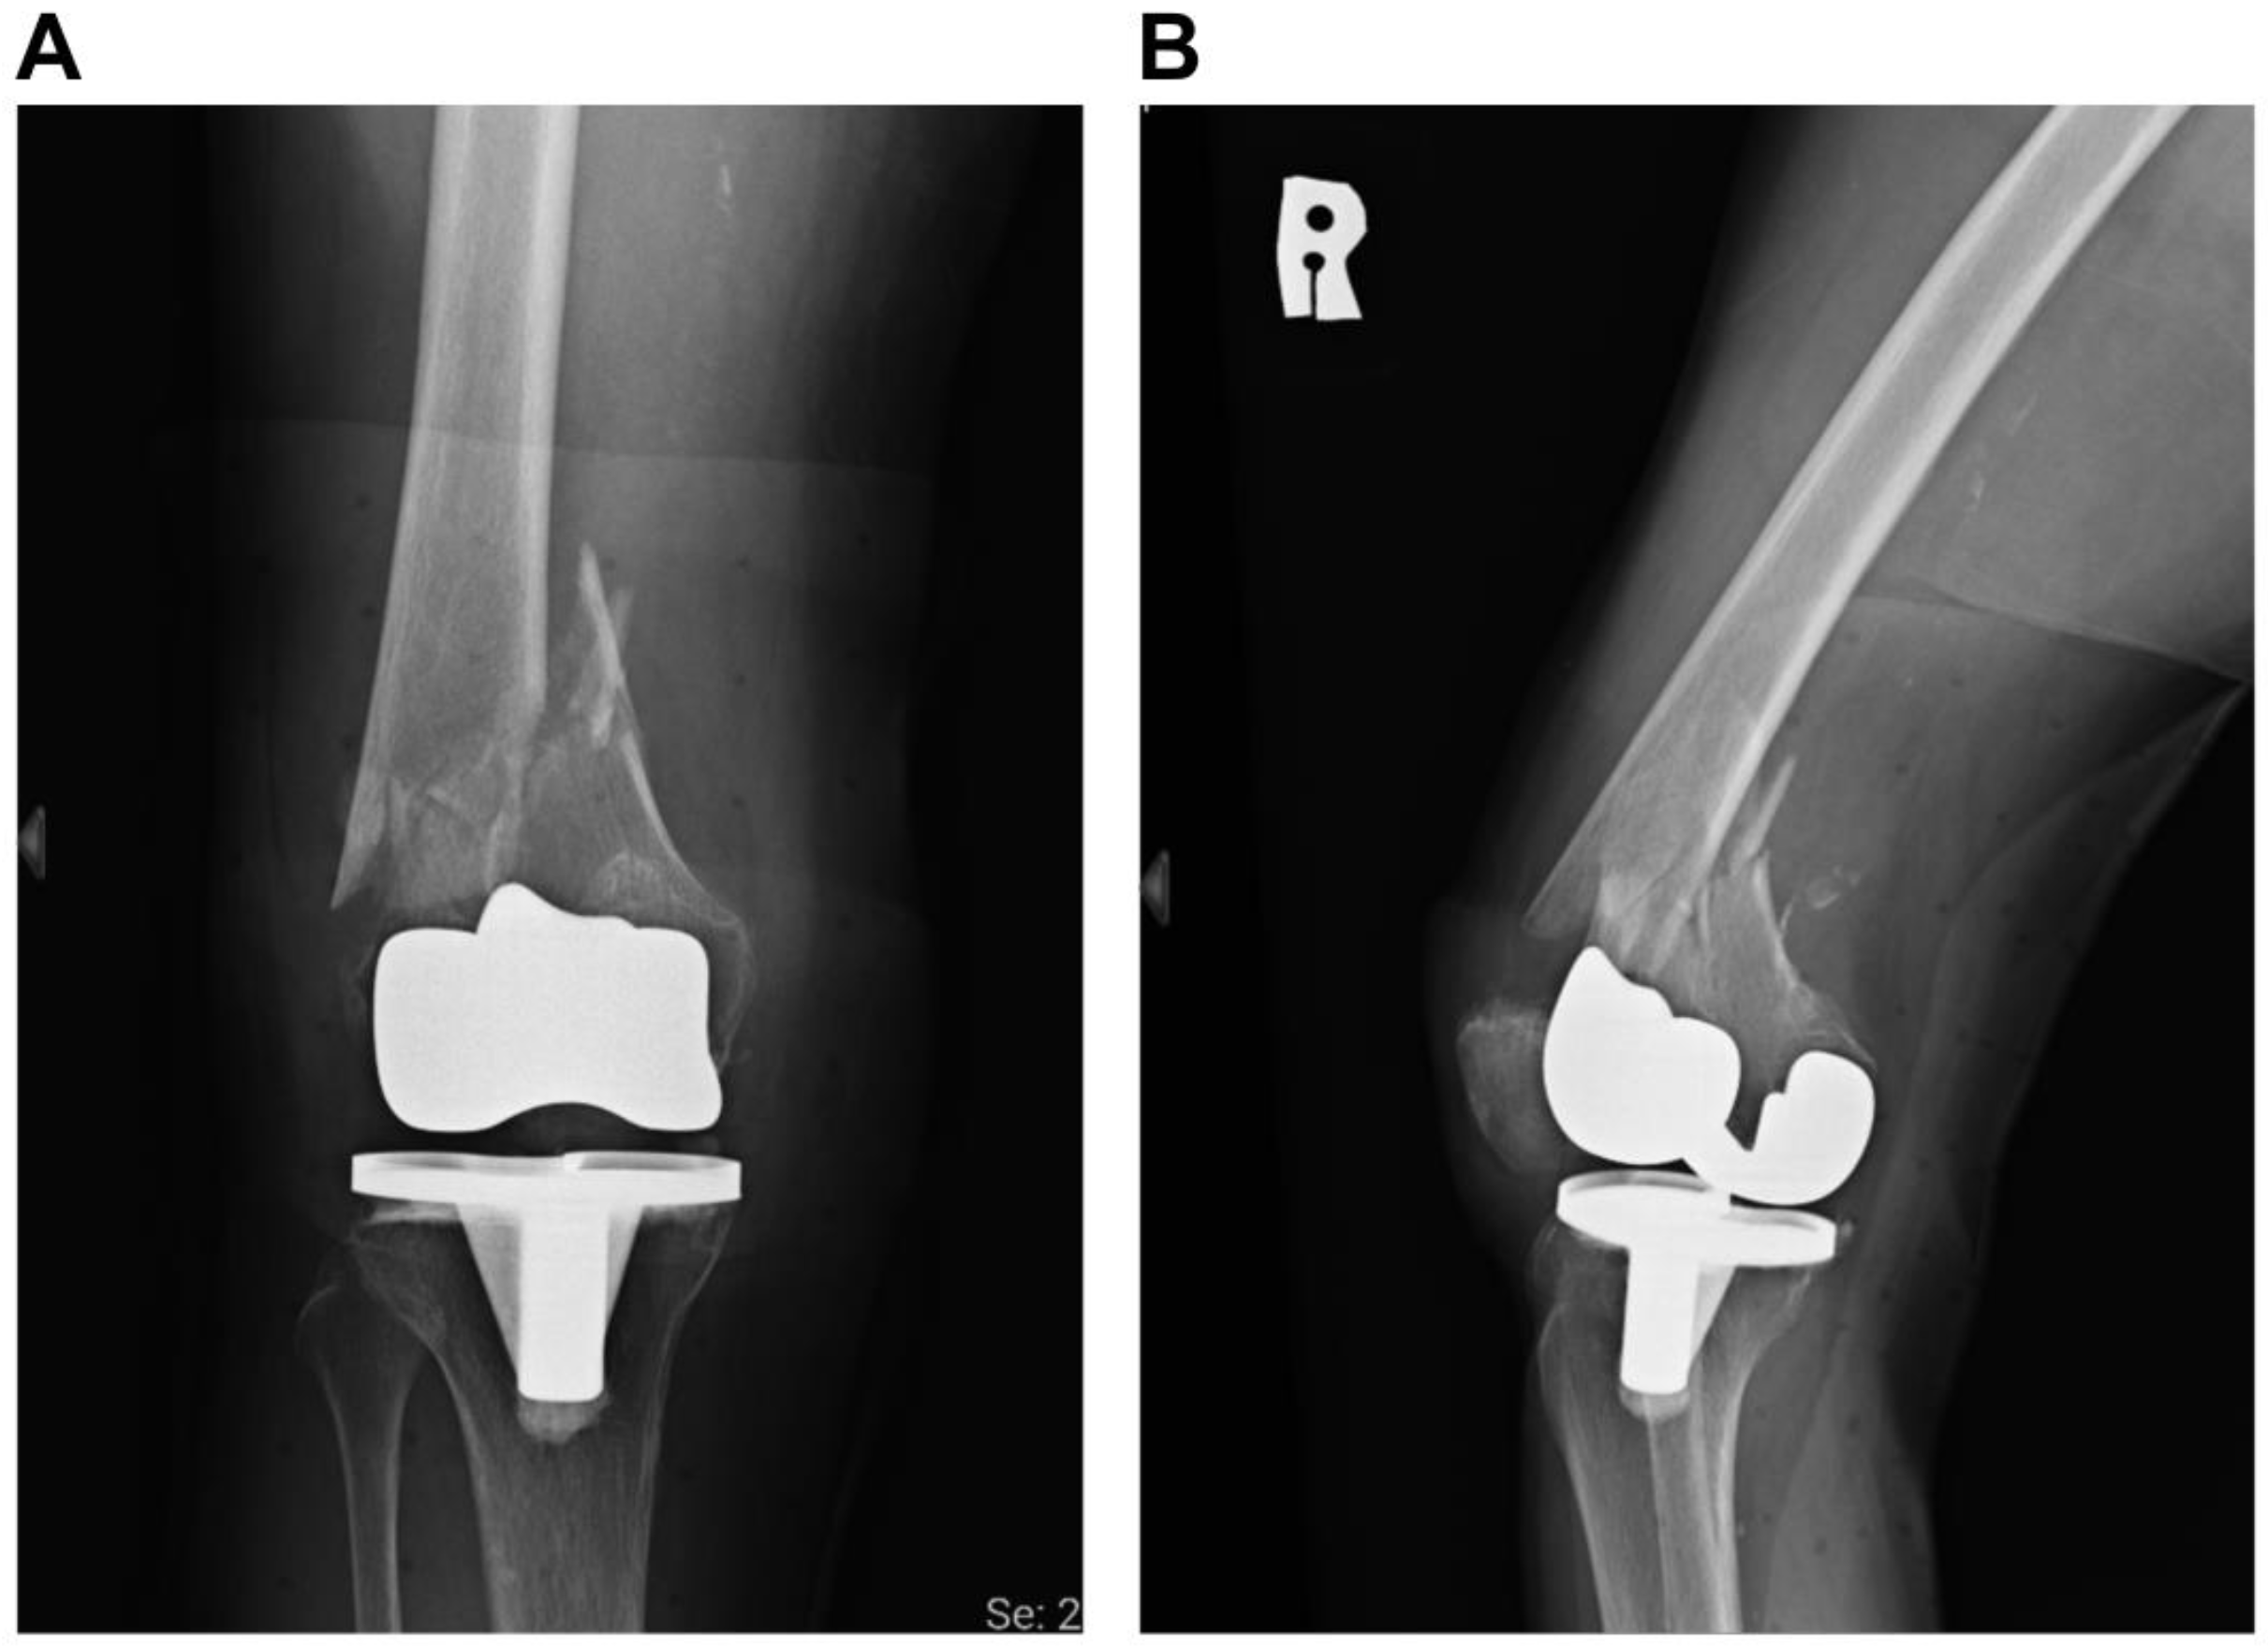

Successful Plate Fixation with Long Intramedullary Fibula Bone Graft for Periprosthetic Femur Fracture: A Case Report

2. Case Report